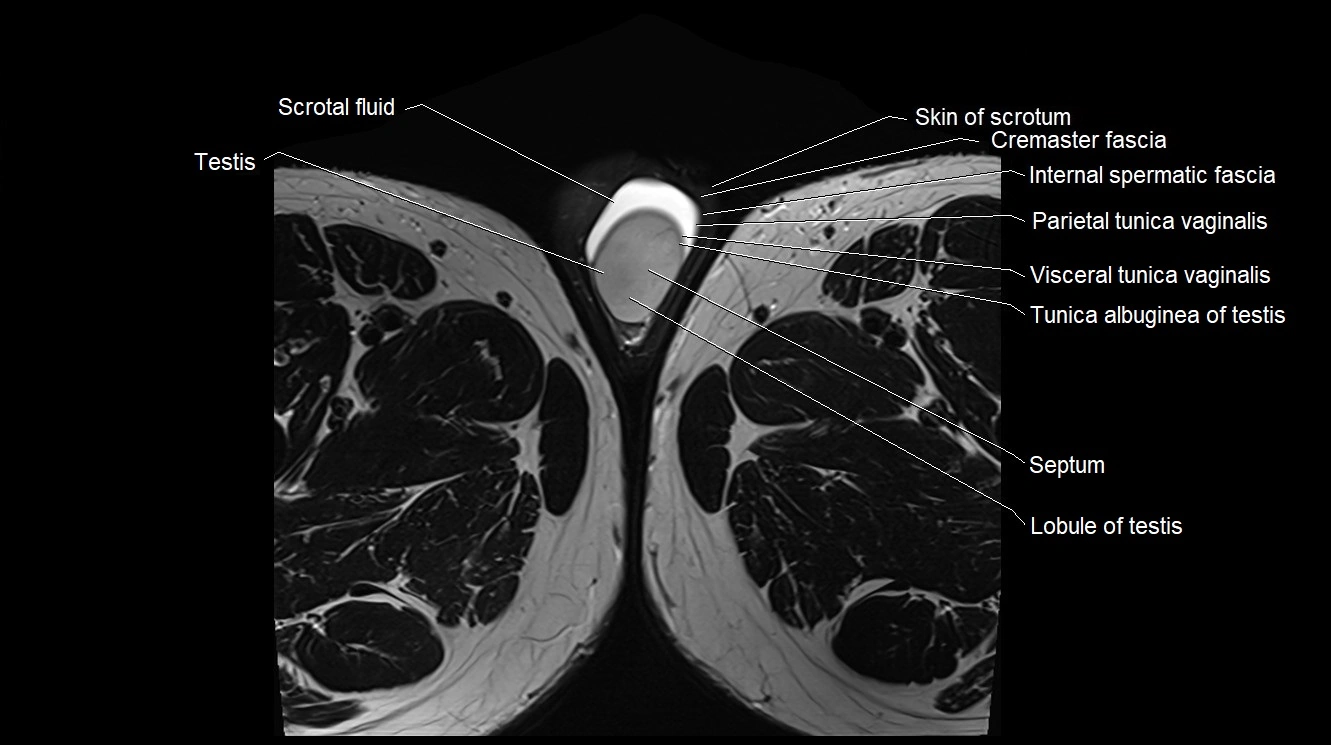

MRI image